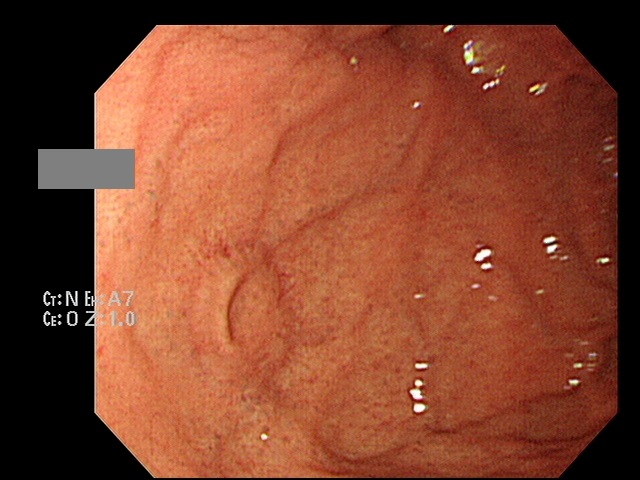

°ËÁø ³»½Ã°æ¿¡¼­ fundus¿¡ ÈñÇÑÇÏ°Ô ÀÖ¾ú½À´Ï´Ù. ¾óÇͺ¸¸é diverticulum °°±âµµ ÇÕ´Ï´Ù. ±×·±µ¥ ±× ÁÖº¯¿¡ ring ¸ð¾çÀ¸·Î angiodysplasia°°Àº°Ô Àִµ¥, ¸·»ó ring shape angiodysplasia Á߽ɺΠ»öÁ¶°¡ ÁÖº¯º¸´Ù »ì¦ ¹àÀº µíÇϰí... Á¡¸·ÀÌ ¹º°¡ ÀçÁúÀÌ ´Ù¸¥ ´À³¦À̶ó°í³ª ÇÒ±î¿ä? ¿©ÇÏÆ° ÀÌ»óÇØ¼­ Á¶½É½º·´°Ô Á¶Á÷°Ë»ç¸¦ Çß½À´Ï´Ù.